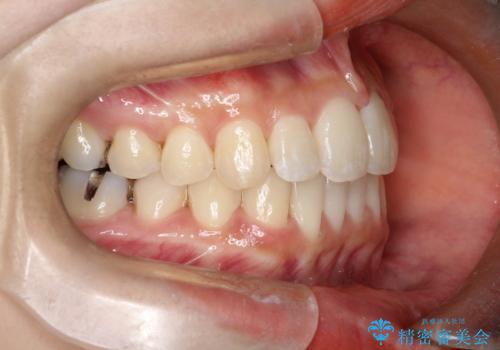

- 前歯の正中離開の改善を希望され来院された患者様です。

初診時の歯並びの状態としては、上下ともに前歯部の中等度のがたつきがあり、特に左上の前歯が1本内側に入り込んでしまっている状態でした。

また、2mm程度の正中離開がありました。

抜歯なし/インビザラインによるマウスピース矯正にて治療を行いました。

内側に入り込んでしまっている歯を出してくることに非常に時間がかかりましたが、一度歯を歯茎の方へ押し込みそして前へ出してくる2段階の治療を行いました。